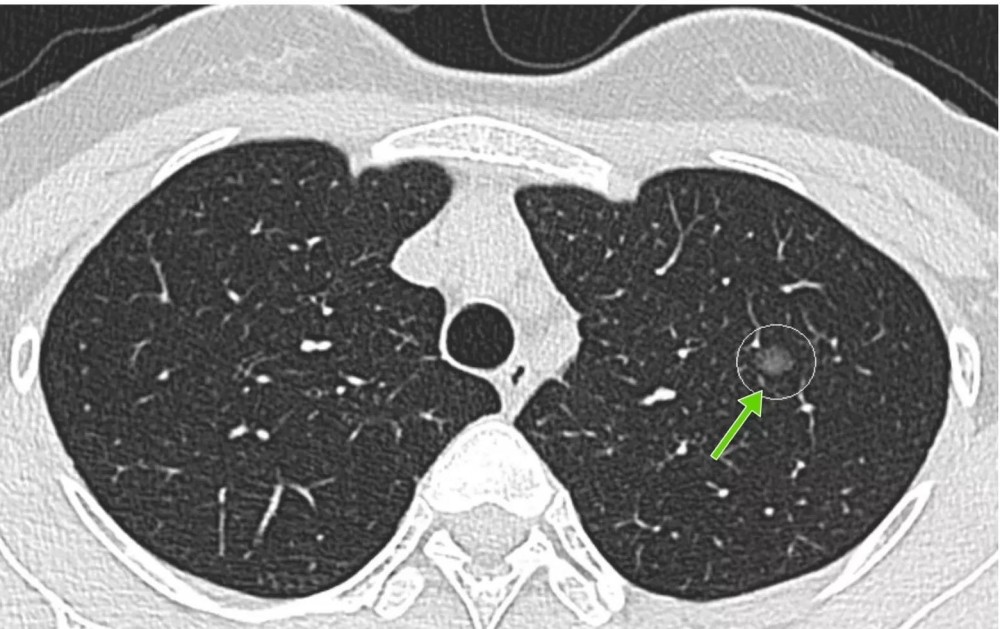

肺部小结节指的是在胸片或者是肺部CT上面,看到的圆形、类圆形的高密度阴影。

一般来说,小于3cm的叫结节,大于3cm的称之为肿块。肺部小结节最常见的原因就是肺部感染,也可能是陈旧性病变,或者是肺结核、结节病,也可能是肺部的恶性肿瘤。如果肺部小结节首先考虑肺部感染的话,可以给予抗生素抗感染治疗两周以后,再复查肺部CT。如果没有变化,就要定期复查,比方说三个月之后还要去做个肺部CT。如果仍然没有变化,半年之后再去做个肺部CT。如果仍然没有变化的话,要在医生指导下决定随访的间期。

如果是大于40岁以上的成人有吸烟史,或者有吸二手烟史,或者家族当中有恶性肿瘤家族病史,这种情况就要定期复查。如果在随访的过程当中,发现结节密度发生了改变,或者结节变大了,或者出现了一些恶变的征象,比方说血管征、空泡征等等,就要进一步检查,进一步明确诊断。